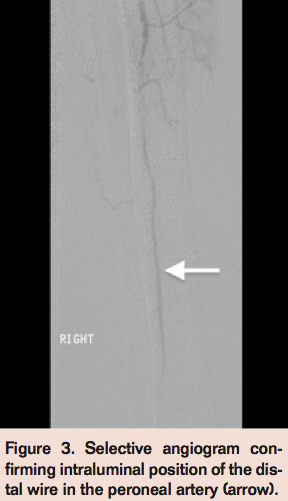

In the setting of CLI with a nonhealing ulcer in the corresponding angiosome, an endovascular intervention of the right TPT occlusion was pursued. A TruePath CTO Device catheter (Boston Scientific) was advanced across the occlusion into the distal peroneal artery (Figure 2). Subsequent angiogram confirmed intraluminal position of the distal wire in the peroneal artery (Figure 3).